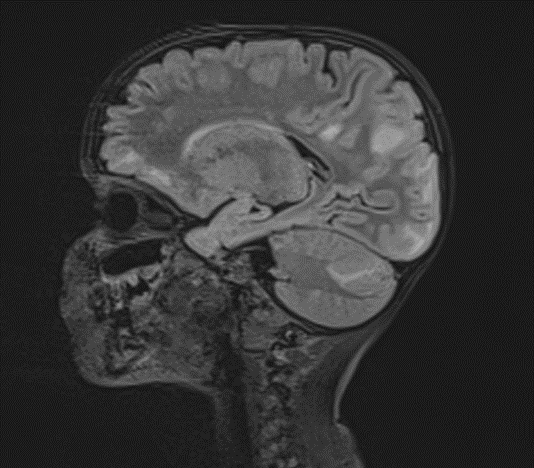

The changes observed are characteristic radiological markers appreciated on DWI, indicative of cytotoxic edema. The DWI changes are considered reliable early signs of acute toxic encephalopathy, specifically methotrexate-related leukoencephalopathy. Post-contrast MR images did not show any abnormal contrast enhancement.

Picture 4.